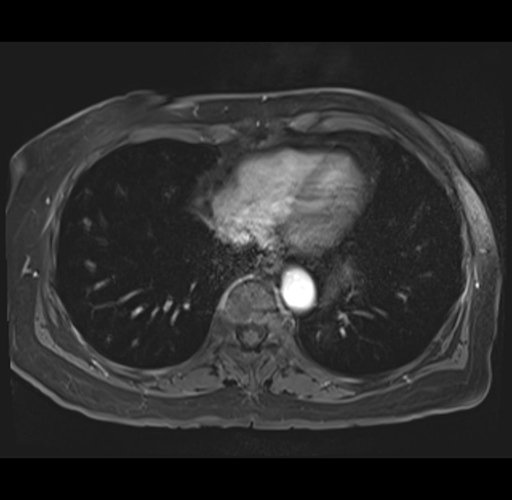

MRI T1

Imaging analysis

Based on your CT findings, which issue(s) would give reason for "planned slowing down moment(s)" in this case?

Considering a standard right hepatectomy procedure, what step(s) of the operation would you do differently in this case?